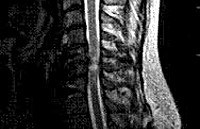

Миелопатия. Обобщенное понятие, используемое в неврологии для обозначения различных по своей этиологии поражений спинного мозга, обычно имеющих хроническое течение. Клинически они могут проявляться нарушениями силы и тонуса мышц, различными сенсорными расстройствами, дисфункцией тазовых органов. Задачей диагностического поиска при миелопатии является выявление причинного заболевания. С этой целью проводится рентгенография позвоночника, МРТ, ЭМГ, ЭНГ, ангиография, анализ ликвора, биохимические исследования крови, ПЦР-диагностика и тд Лечебная тактика основана на терапии основного заболевания, симптоматическом лечении и реабилитации при помощи ЛФК, механотерапии, массажа, иглоукалывания и физиотерапии.

Диагностический алгоритм при выявлении признаков миелопатии направлен на исключение другой, сходной по клиническим симптомам, патологии ЦНС и установление этиологического фактора, лежащего в основе дистрофических изменений спинного мозга. Он включает общий и биохимический анализ крови, рентгенографию позвоночника, МРТ позвоночника, электромиографию (ЭМГ), электронейрографию (ЭНГ), исследование вызванных потенциалов, МР- или КТ-ангиографию спинного мозга, люмбальную пункцию.